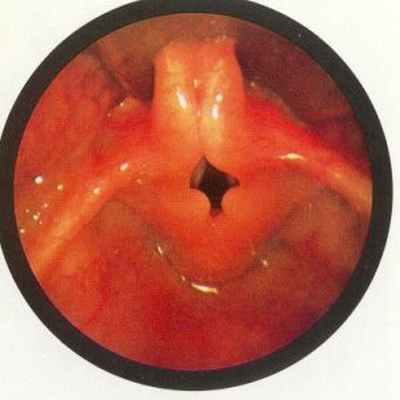

Патогенез врождённого стридора связан со спадением надгортанника и черпаловидно-надгортанных складок, а также смещением кпереди избыточной слизистой оболочки клиновидных хрящей. Стридор возникает в результате спадения надголосовых структур на вдохе, появление звука обусловлено изменением плавного потока воздуха на турбулентный. При выдохе надголосовые структуры смещаются кнаружи, поэтому выдох происходит без помех, движение воздуха плавное и стридора нет.

Фиброларингоскопия — метод исследования гортани с помощью гибкого эндоскопа после предварительного нанесения местного анестетика на слизистую носа или через полость рта у маленьких детей. Трубочка вводится до голосовой щели и на этом уровне оценивается её просвет на вдохе-выдохе. Плач не препятствует осмотру. Данный метод считается достаточно информативным, осмотрев с его помощью просвет гортани, можно определить причину стридора. Фиброларингоскопия не требует специальной подготовки, но желательно выполнять её спустя некоторое время после кормления.

Важно проведение эндоскопической ларингоскопии, за счет гибкого зонда, который вводится через нос ребенка, просматривается деформация надгортанника и черпаловидных хрящей, а также их провисание при вдохе.